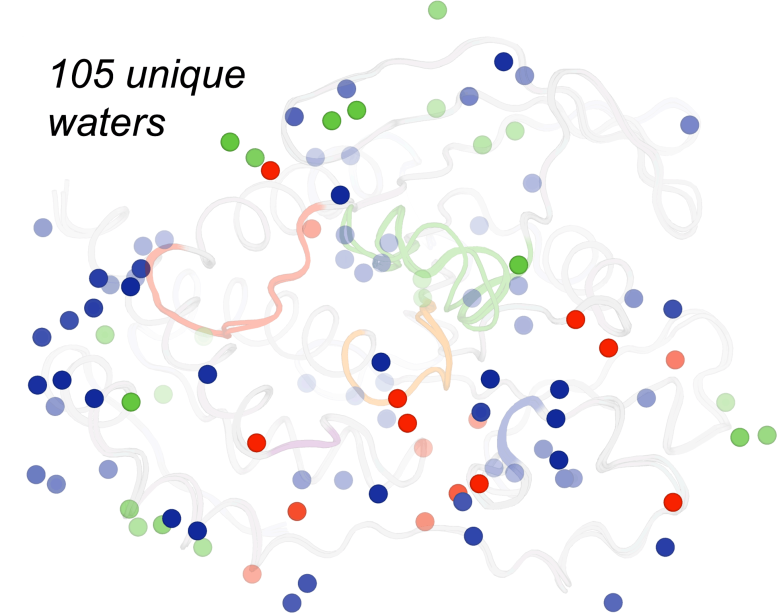

水分子位置常对理解蛋白弹性和药类分子影响蛋白结构功能能力很重要在这次研究中,不同独特水分出现在蛋白质表面,实验干扰不同,如高温(红化)、高压(绿化)或缺省条件(蓝化),为这些问题提供补充洞见嘉宾:Ali Ebrahim和Liliana Guerrero